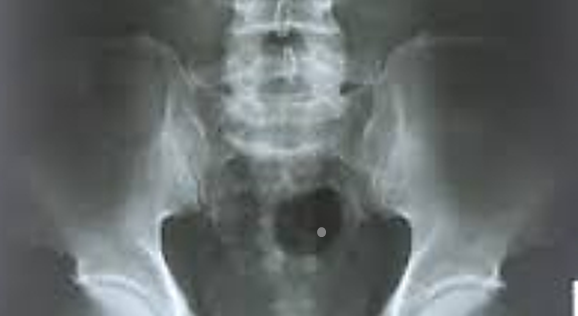

얼마 전 건강검진의 엑스레이 사진 속에 하얀 점이 방광 부분에 보였다.

작은 결석이 생긴 것 같다고 의사선생님이 말씀하셨고 아주 작아서 자연스럽게 빠질 수 있도록 물을 많이 마시라고 하셨다.